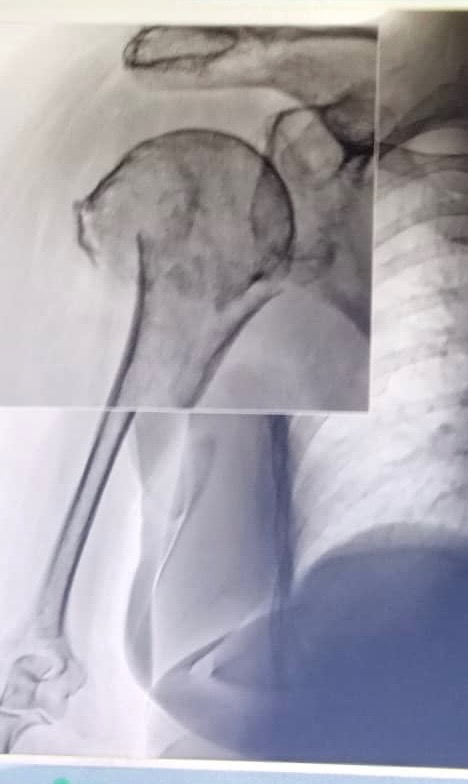

Last week, Mima fell and fractured her proximal humerus (upper arm and shoulder). The injury is severe, and surgery is now medically necessary to restore her mobility and relieve her pain.